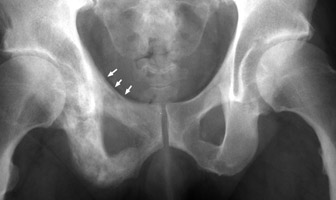

AP radiographs of the pelvis with changes characteristic of Paget's disease throughout the right hemipelvis. Notice the thickening of the right pelvic brim (ileopectineal line) as compared to the left. Thickening of the pelvic brim, or arcuate line (ileopectineal line) seen in patients with Paget's disease. The ridge of bone around the pelvic brim, when osteoblastic reaction occurs, adds to the normal sclerotic density of this area. This is a useful sign in distinguishing Paget's changes from metastatic disease.

AP pelvis - Click on the image for a larger versionAAP pelvis - Click on the image for a larger versionB